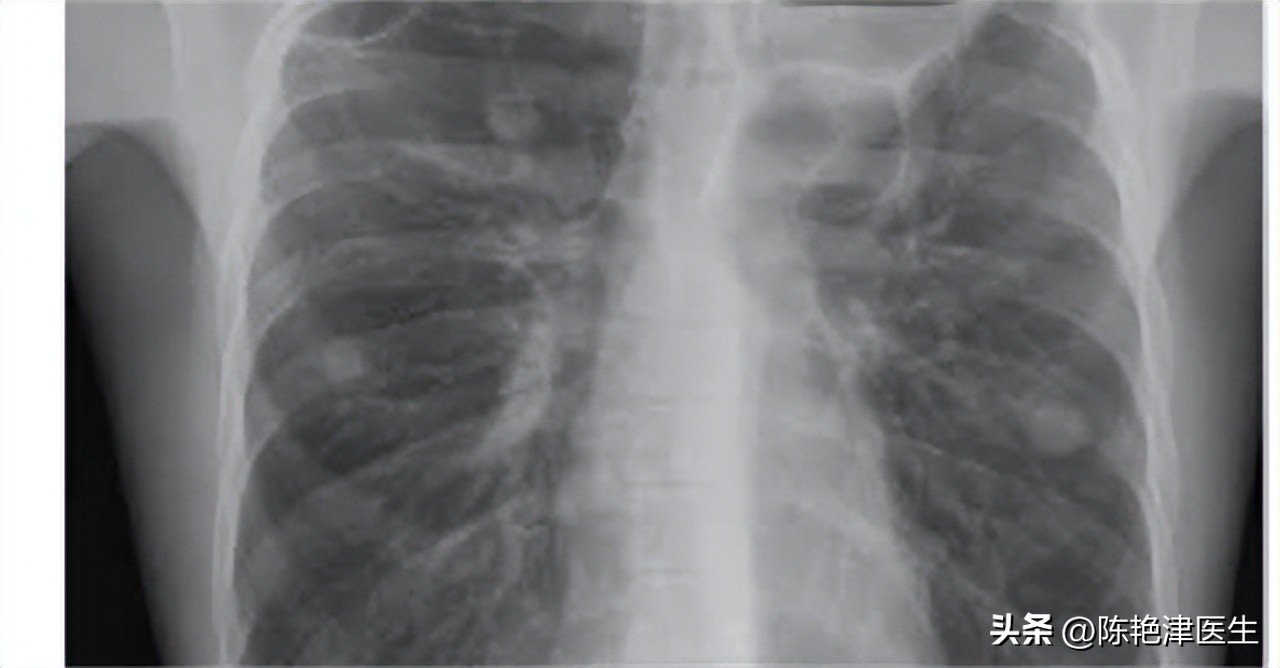

医生接诊后先给小王安排了一次胸片,看看肺部情况。

胸片结果出来后, 医生告诉小王,胸片上显示小王的肺部有一处肺大疱,可能是他的哮喘频繁发作导致的,而且小王的胸闷可能也与之相关。

一般来说,对于大部分 无症状 、偶然发现的肺大疱,通常 不需要进行治疗 ,只需要定期 复查随诊 ,观察肺大疱有无进展即可。目前临床上常用的检查手段有以下三种。一种是 X线 检查,最廉价又最常用,但对于直径较小的肺大疱不易检出;